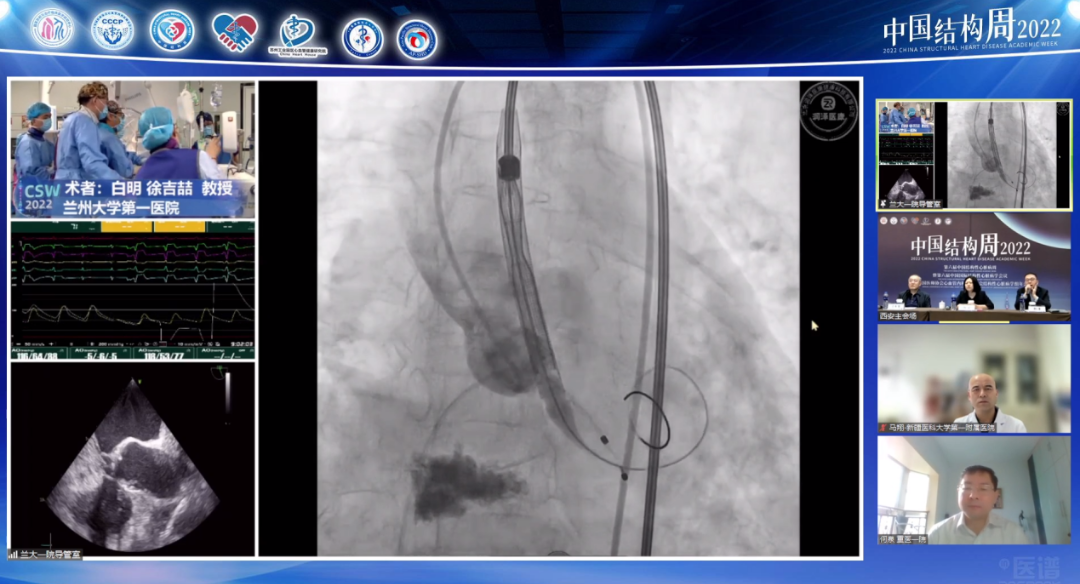

空军军医大学西京医院陶凌教授团队(术者:李飞教授)带来一例感染性心内膜炎重度AS患者。

病例介绍:男性患者65岁,主诉劳累后胸痛、胸闷、气短10余年,加重7月余。

患者10余年前心脏彩超检查示主动脉瓣狭窄,7月前气短症状明显加重,夜间端坐呼吸,心脏彩超示主动脉瓣重度狭窄。合并症2型糖尿病病史5年,脑梗死病史2月余,泌尿系感染1月余、外周血管溃疡。

手术策略主要讨论如下:

血管存在溃疡、夹层,入路及外周并发症如何处理?

Type1型二叶瓣,严重偏心性钙化病变,瓣膜选择及释放高度如何?

预扩张及后扩张策略?

手术可能存在的并发症及应对策略?

针对本例患者,术者团队介绍了特殊情况,食道超声检查示无冠窦窦壁有囊性结构,考虑存在感染,血流通过无冠窦窦壁喷射到囊腔里面,随后询问病史患者自述有泌尿系感染1月余,故考虑合并感染性心内膜炎,囊性结构是陈旧性赘生物。有专家认为患者有脑梗死病史2月余,系囊性赘生物脱落所致。

与会专家针对食道超声发现的囊性结构展开激烈探讨,对于泌尿系感染和脑梗死的病因认为是赘生物脱落所致,在此情况下,建议该患者不太适合TAVR手术。李飞教授同意现场探讨内容,下一步策略计划再次评估CTA,局部采血后血培养,核磁明确,考虑到患者心衰严重,首先保守治疗后,选择SAVR(外科主动脉瓣置换术)还是抗炎后TAVR具体情况深入分析后在做抉择。但有专家更倾向于外科开胸换瓣,可以进一步分析病理。